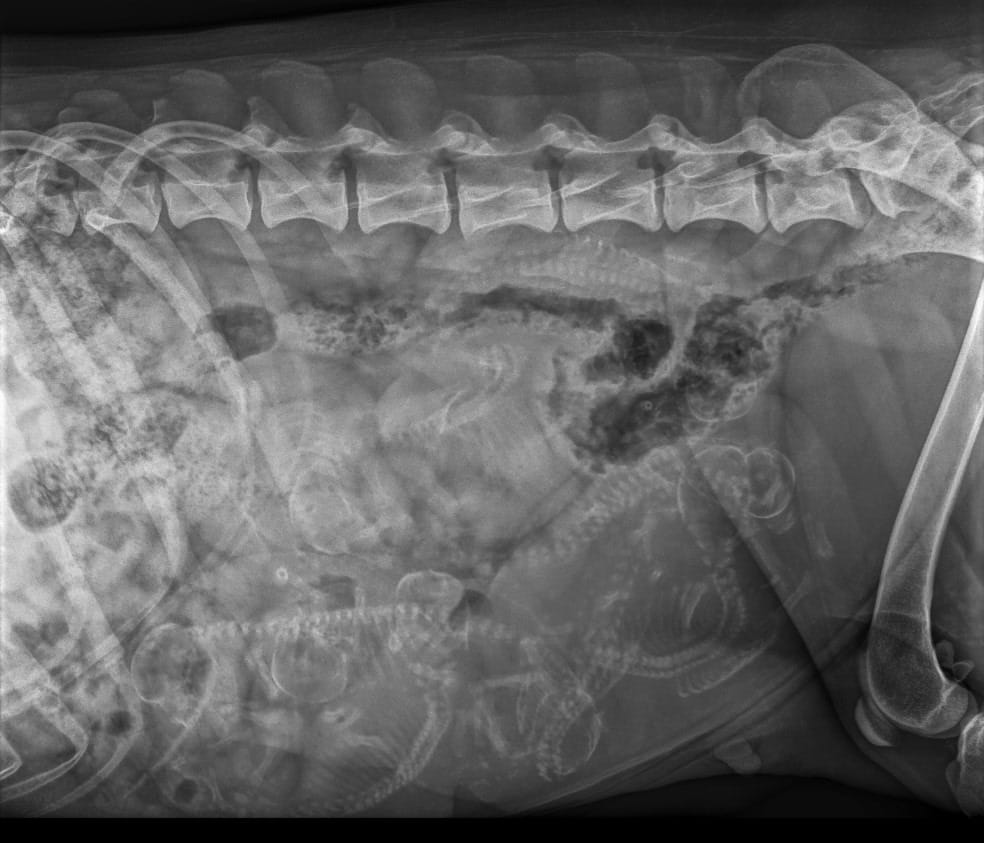

Pentueen isä on norjalainen komistus Ridgedogs In Love With Elvis ja emä kantanarttumme Aries Khan Margaret Tatcher Of Lumottu. Pentueen molemmat vanhemmat on luustokuvattu terveeksi lonkkien, kyynärien ja selän osalta. Yhdistelmän sukusiitosprosentti on 0 % 5:ssä sukupolvessa ja 1,9 % 10:ssä. Lämmin kiitos Elviksen kasvattajalle Ann Kristin Wien Stubberudille ja toiselle omistajalle Vibeke Peelen-Aubertille, että saamme toteuttaa tämän yhdistelmän!

| Selkä: | LTV0, SP0, VA0 |

| Selkä: | LTV1, SP0, VA0 |

| Selkä: | LTV3, SP0, VA0 |

| Selkä: | LTV0, SP0, VA0 (1 blokkinikama) |